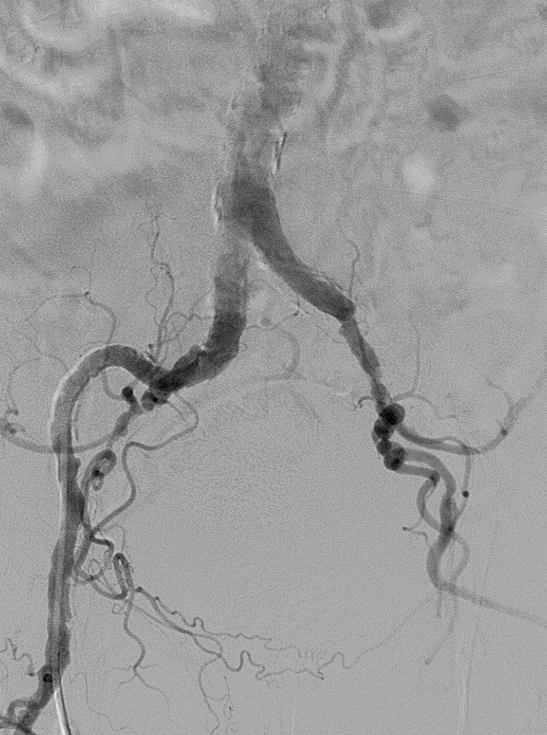

★ Case 1

noproximal stump in SFA,>250mm

★ Case 2

significantdistal collaterals